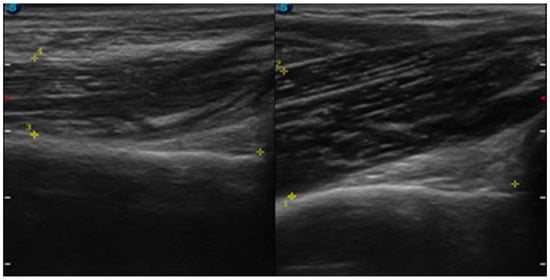

| July | Symptoms: brachialis muscle atrophy (Figure 1 and Figure 2) (pain 4/10 NPRS). Assessment: medical history, physical examination, ultrasound (orthopaedic surgeon). Diagnosis: unspecified soft tissue diseases associated with their use overload and overexertion (M70.9 ICD). Treatment: pharmacological treatment, avoid full weight-bearing. Effects: no positive therapeutic effect. |

| October | Symptoms: episodic of more severe pain, paraesthesia, tingling, numbness and burning sensations of right upper limb, (pain 3/10 NPRS). Assessment: medical history, physical examination (another orthopaedic surgeon), shoulder (Figure 3) and elbow MRI order (the same orthopaedic surgeon), cervical spine MRI order, electromyography, nerve conduction study (Table 2 and Table 3) (another orthopaedic surgeon), medical history, physical examination, ultrasound (another physiotherapist). Diagnosis: mononeuropathy of the upper limb, unspecified (G56.9 ICD) (orthopaedic surgeon), PTS suggestion (physiotherapist) Treatment: orthopedy surgeon: physiotherapy (massage, muscle relaxation, electrostimulation, exercises); physiotherapist recommendation: neurodynamic techniques. Effects: no positive effect. |

| THss BM | affected | 11.61 mm | 11.77 mm |

| non-affected | 18.79 mm | 18.74 mm | |